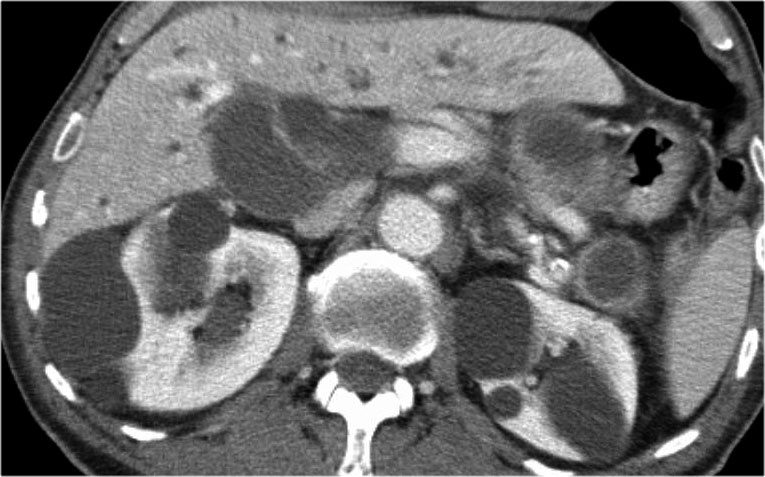

CT cho thấy hai nang lớn ở bệnh nhân nữ 45 tuổi có tiền sử chấn thương (hình).

Lưu ý hình ảnh thâm nhiễm mỡ trong khoang sau phúc mạc (mũi tên).

Kết hợp đặc điểm hình ảnh với tiền sử lâm sàng, rất có khả năng đây là các nang giả tụy do chấn thương.